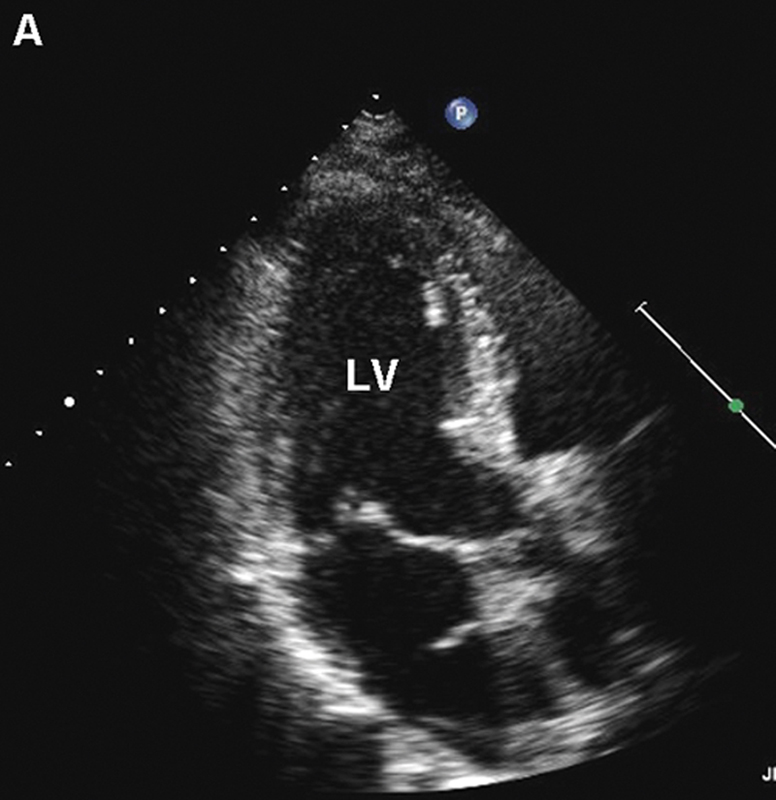

فحوصات تشخيصية لبعض امراض القلب والشرايين التاجية